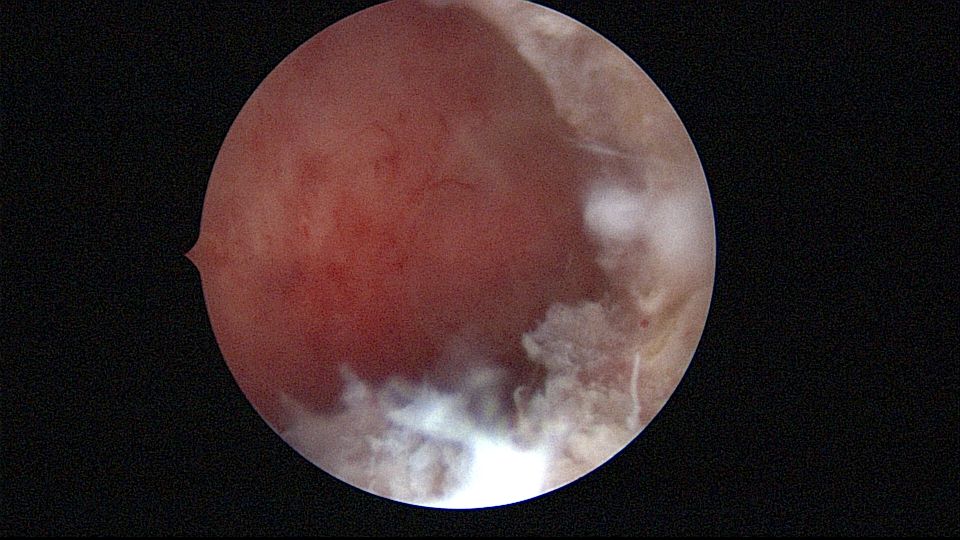

患者25岁,G1P0,停经52天,稽留流产,B超宫内偏右查见大小约2.4cmx1.0cmx1.7cm孕囊回声,形态规则,内可见直径约0.4cm的卵黄囊回声,未见胎芽,孕囊旁肌层最薄处厚约0.5cm,子宫中下段回声连续性欠佳,似可见一分隔回声。2021年7月宫腔镜探查,胚胎着床于宫腔前壁偏右,宫颈内口及宫腔左侧壁粘连。清除妊娠组织,单极电针分粘,恢复宫腔形态,双侧输卵管开口显露(第一次怀孕,宫腔粘连原因?)。2022年7月自然妊娠,2023年3月足月剖宫产分娩。2024年12月,外院人流术后1+月,宫内残留,与后壁肌层分界欠清,局部血流信号增多,到我院宫腔镜切除残留组织(后3张图片)。现患者30岁,G3P1。宫腔粘连常常不能阻止妊娠,但胚胎停育发生率增加。